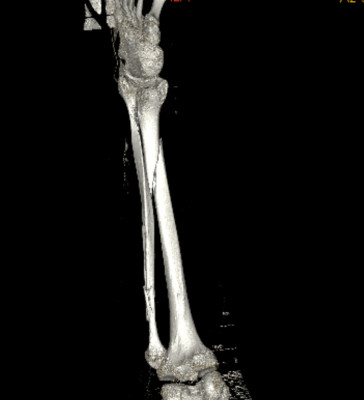

Bij deze mijn ervaring van 9 okt 2025

Ik zou je eerder een e-fiets van 25km/u aanraden, ideal compromis tussen veilgiheid, afstand en prijs.

Als ervaren motard die geregeld laagvliegt met race machientjes... Ik heb nu bang op een speed pedelec